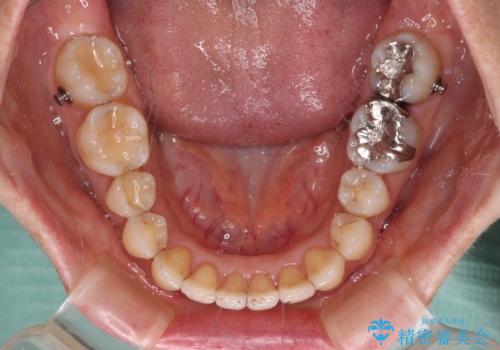

インビザライン・ライトは提供されるマウスピースの数に制限があり、通常のタイプよりもマウスピース提供期間が短くなっている一方、安価に治療を行うことができるプランです。

治療のゴールも変更できないため、軽微な歯列不正や、後戻り改善などに適しています。